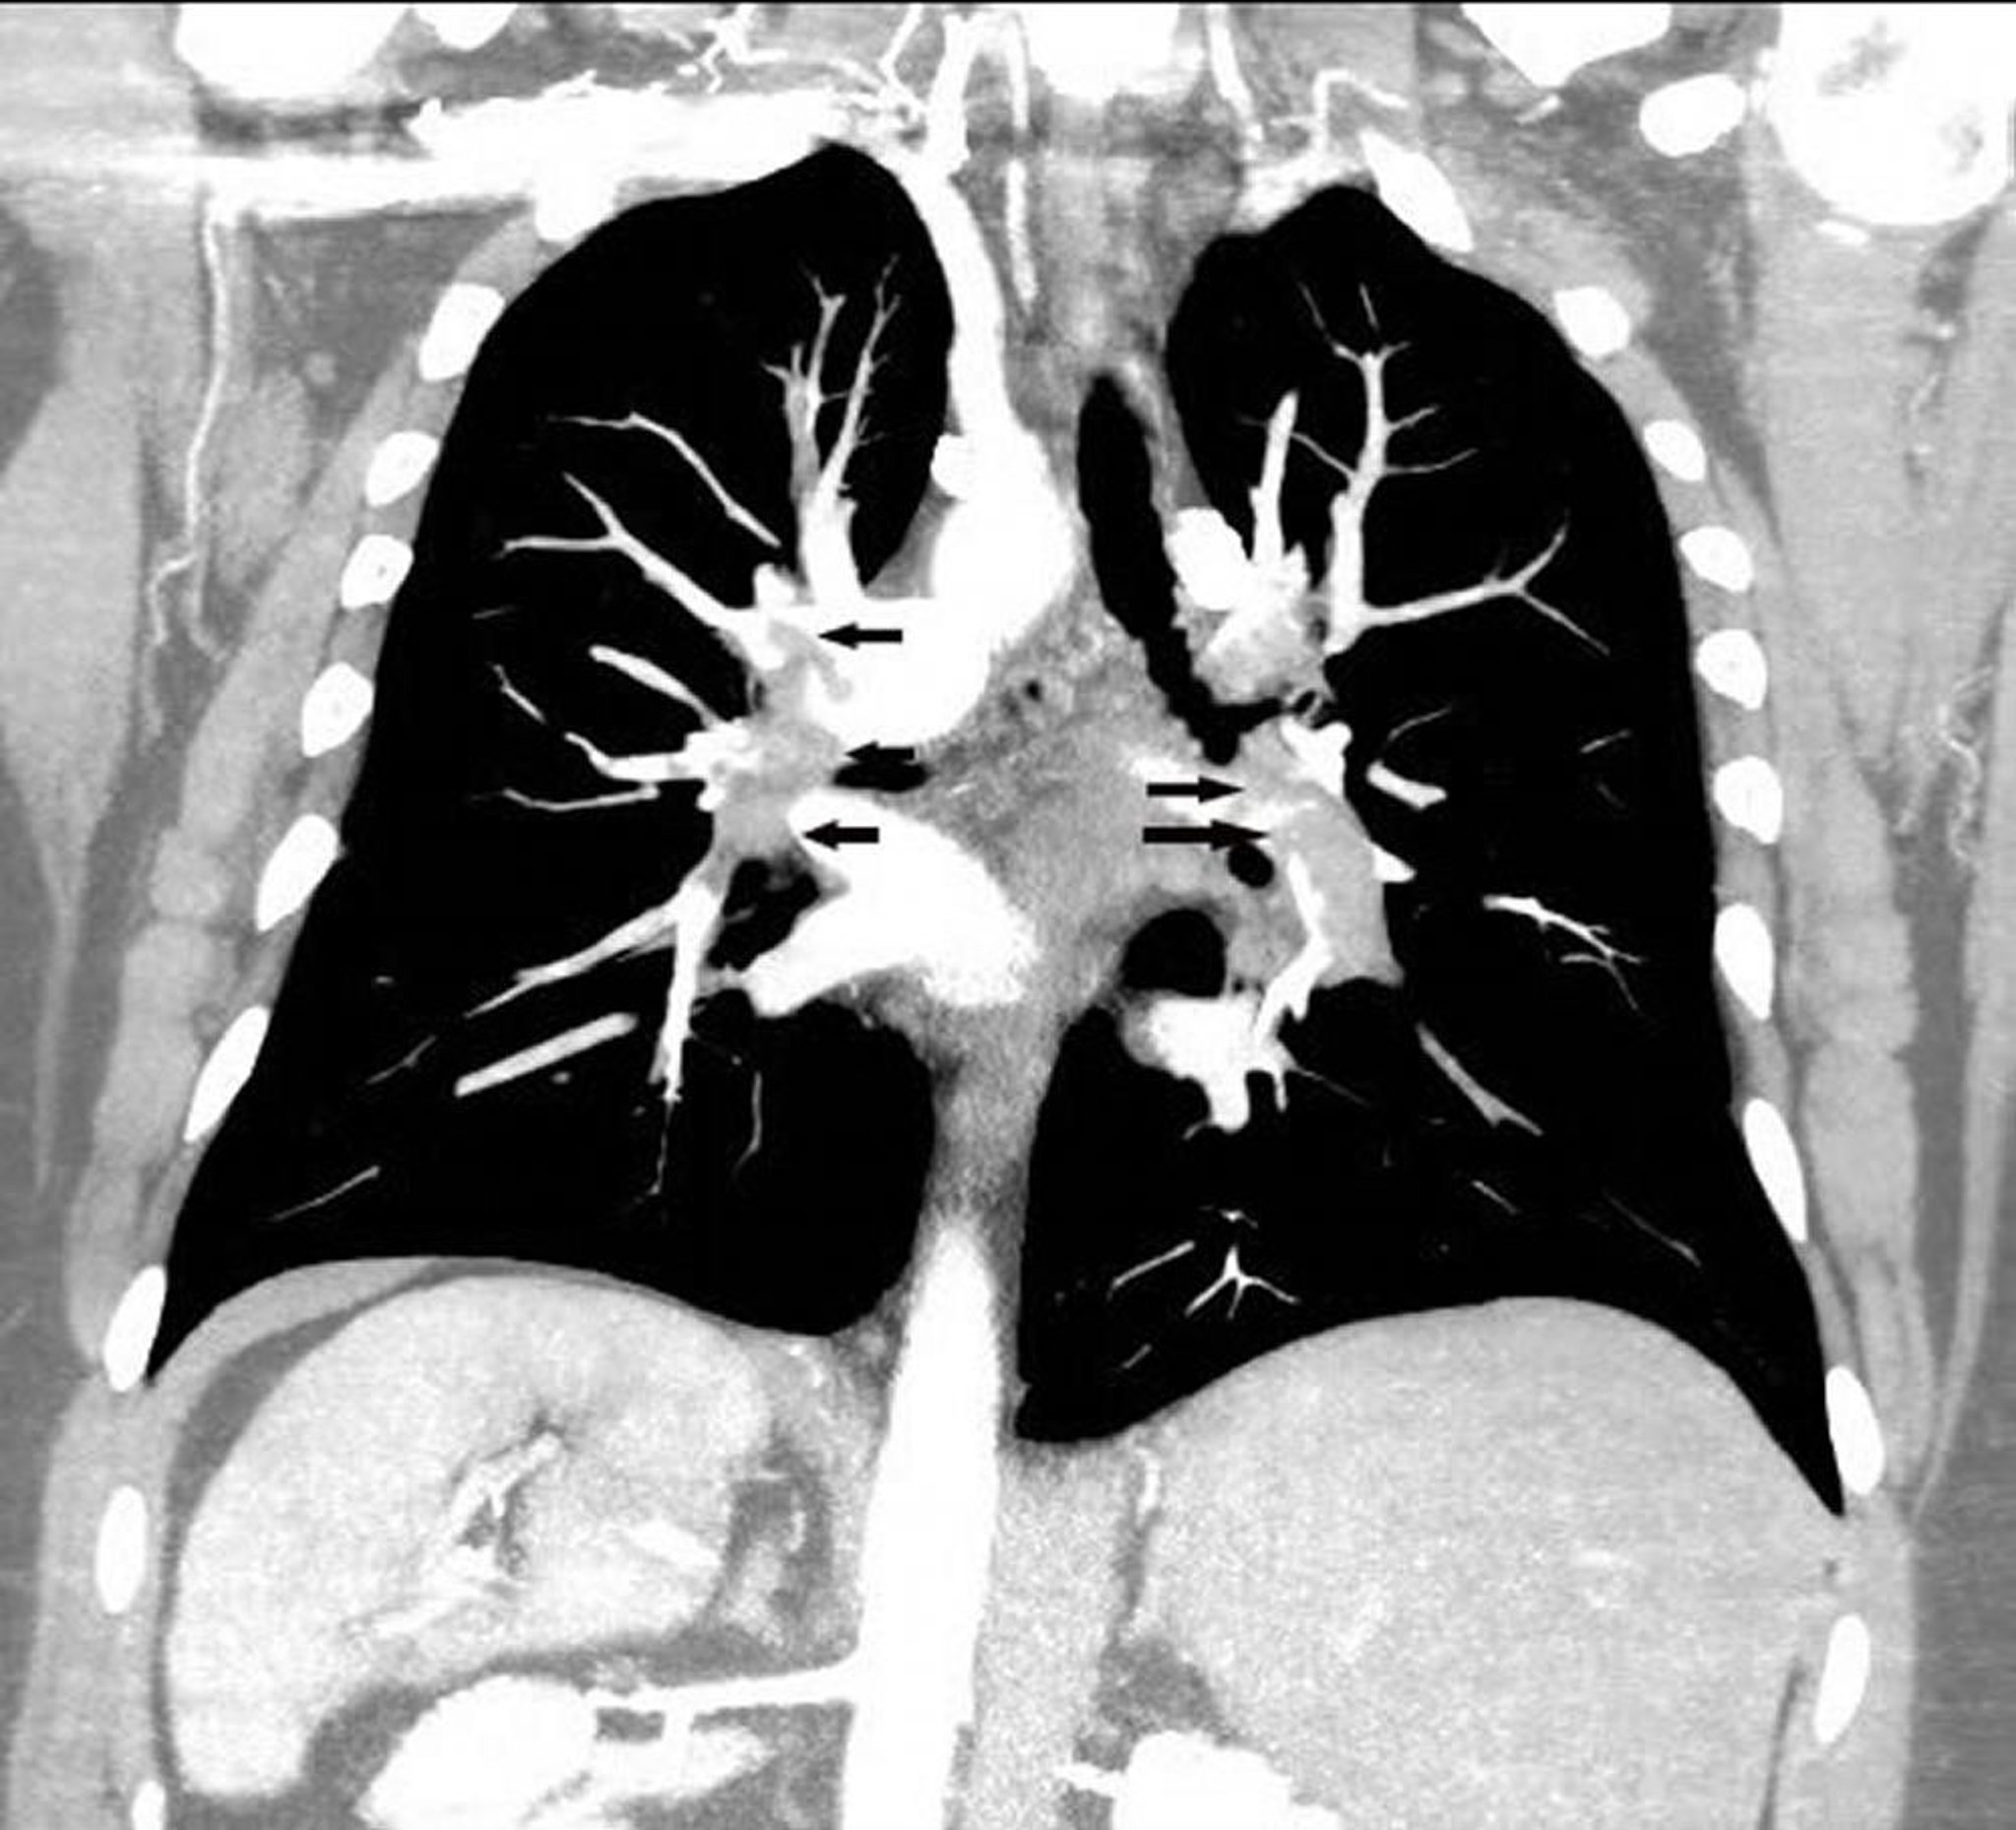

Angiografia polmonare con ricostruzione coronale TC

La ricostruzione coronale di un'angioTC polmonare mostra un ampio embolo polmonare in entrambe le arterie polmonari (frecce).

Image courtesy of Hakan Ilaslan, MD.